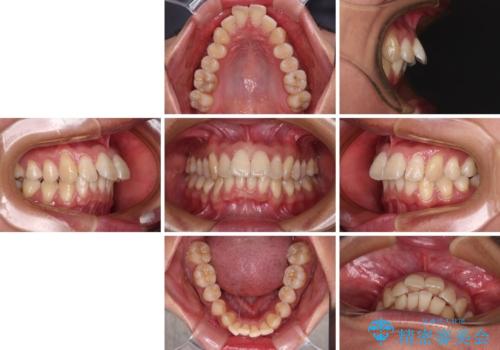

- 上顎前歯の突出感を気にして来院された患者様です。

舌の突出癖の影響で、歯列が前方に飛び出いた形態となっている状態でした。

抜歯矯正とするような歯列ではないため、舌のトレーニングを行いながら歯列を側方に拡大させることで口元の突出感を改善することとしました。

横顔は元々突出した印象ではなかったのですが、上顎前歯の角度が改善したことで、唇の閉じにくさが改善されました。